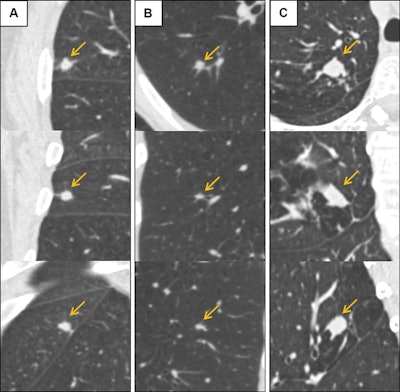

Low-dose CT images show examples of screen-detected pulmonary nodules (arrows) where the deep-learning algorithm provides a more accurate malignancy risk estimation than the Pan-Canadian Early Detection of Lung Cancer (PanCan) model on axial (top), coronal (middle), and sagittal (bottom) planes. (A) Image shows a 9.7-mm malignant nodule (arrows) with a high deep-learning risk score (32.3%) and low PanCan risk score (3.2%) in a 74-year-old male participant diagnosed with squamous cell carcinoma. (B) Image shows a 6.8-mm malignant nodule (arrows) with a high deep-learning risk score (15.9%) and low PanCan risk score (1.2%) in a 71-year-old male participant diagnosed with adenocarcinoma. (C) Image shows a 19 mm benign nodule (arrows) with a low deep-learning risk score (4.7%) and high PanCan risk score (32.7%) in a 50-year-old female participant. Additional PanCan input features used in the model were retrieved from original trial records, as follows: (A) negative for family history of lung cancer, negative for emphysema, negative for spiculation, negative for upper lobe location, nodule count: four; (B) negative for family history of lung cancer, negative for emphysema, negative for spiculation, negative for upper lobe location, nodule count: two; (C) negative for family history of lung cancer, positive for emphysema, negative for spiculation, positive for upper lobe location, nodule count: one. Images and caption courtesy of the RSNA.Low-dose CT images show examples of screen-detected pulmonary nodules (arrows) where the deep-learning algorithm provides a more accurate malignancy risk estimation than the Pan-Canadian Early Detection of Lung Cancer (PanCan) model on axial (top), coronal (middle), and sagittal (bottom) planes. (A) Image shows a 9.7-mm malignant nodule (arrows) with a high deep-learning risk score (32.3%) and low PanCan risk score (3.2%) in a 74-year-old male participant diagnosed with squamous cell carcinoma. (B) Image shows a 6.8-mm malignant nodule (arrows) with a high deep-learning risk score (15.9%) and low PanCan risk score (1.2%) in a 71-year-old male participant diagnosed with adenocarcinoma. (C) Image shows a 19 mm benign nodule (arrows) with a low deep-learning risk score (4.7%) and high PanCan risk score (32.7%) in a 50-year-old female participant. Additional PanCan input features used in the model were retrieved from original trial records, as follows: (A) negative for family history of lung cancer, negative for emphysema, negative for spiculation, negative for upper lobe location, nodule count: four; (B) negative for family history of lung cancer, negative for emphysema, negative for spiculation, negative for upper lobe location, nodule count: two; (C) negative for family history of lung cancer, positive for emphysema, negative for spiculation, positive for upper lobe location, nodule count: one. Images and caption courtesy of the RSNA.